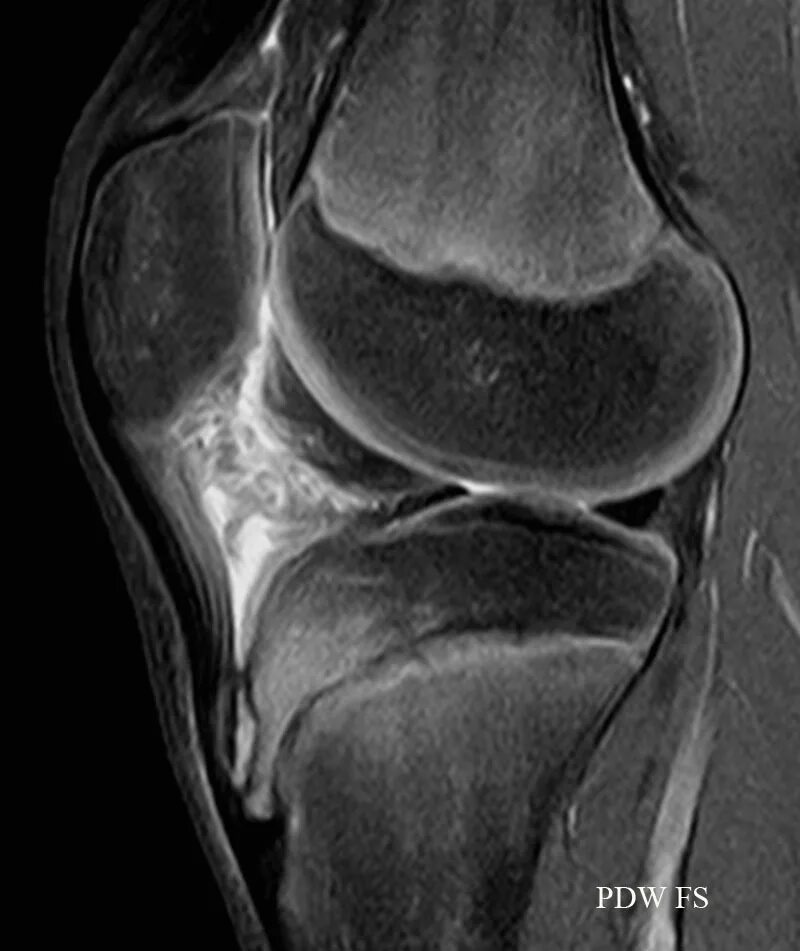

Мрт коленного сустава одежда